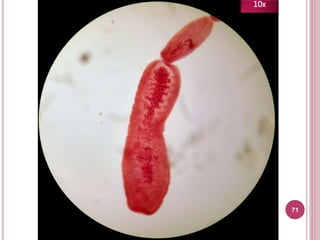

71

Características

 Útero racemoso

 Poro genital posterior

Tiene útero

racemoso

(¡Parece un

racimo!)